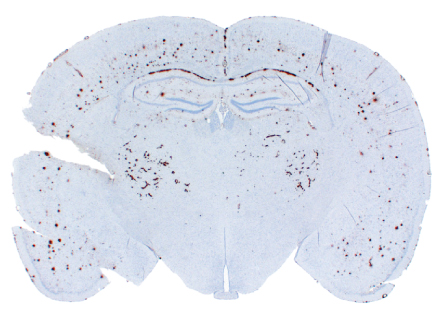

In the study, the researchers injected purified A-beta protein to seed one side of mice’s brains and monitored it with a fluorescent molecule that became visible as the protein accumulated. After about 300 days, the A-beta had accumulated throughout the brain, similar to what happens in Alzheimer’s. “It really does spread,” says study coauthor Kurt Giles of UCSF. “We inoculate in one part of the brain but the pathology spreads through the whole brain.”